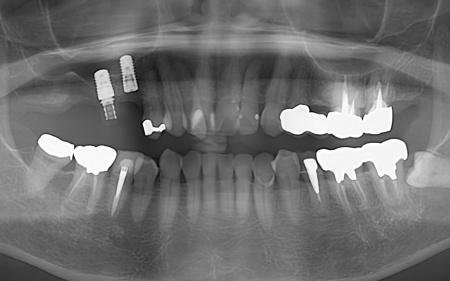

| カウンセリング・診断結果 | 拝見したところ、右上の歯には、欠損部位前後の歯を土台として橋を渡すように連結した被せ物「ブリッジ」が装着されていました。 しかし、土台となっている手前の歯(第2小臼歯)は歯根が割れており、同じく土台となっている奥の歯(第2大臼歯)は歯根の先に膿の袋ができる「根尖病巣(こんせんびょうそう)」が認められます。 さらに、ブリッジ部位の歯茎は腫れ、痛みもあるとのことでした。 かかりつけの歯科医院では、細菌感染を抑える薬を飲んだり、歯を少し削って噛み合わせを調整したりして様子を見ていましたが、口腔内の状態が改善せず、次は抜歯をする必要があると説明を受けたそうです。 また抜歯後に歯を補う方法のひとつにインプラント治療がありますが、患者様の場合は治療に必要な骨量が確保できないため難しいとされ、取り外し式の入れ歯になるとのことでした。 患者様はかかりつけ医からの説明が十分でないと感じていたため、当院にセカンドオピニオンで来院されています。 以上のことから、まずはブリッジ周辺の治療を行ったのち、欠損部を補う治療方法をしっかりと検討する必要があると診断しました。 |

| 行ったご提案 ・治療内容 | 痛みが出ているブリッジ周辺の治療として、ブリッジの土台となっていて、歯根が割れている手前の歯(第2小臼歯)は抜き、根尖病巣を発症している奥の歯(第2大臼歯)は、根管治療を行います。 根管治療とは、感染した神経を取り除いて、歯根内部を清掃・消毒する治療方法のことです。 抜歯と根管治療を行ったあとは、欠損部を補うために、2本のインプラントを埋入する方法を提案しました。 インプラントを埋入するために必要な骨量が足りない場合は、鼻の空洞(上顎洞)の粘膜を少しずつ押し上げて骨を増やす「ソケットリフト」を併用することもお伝えしています。 インプラント治療のメリット インプラント治療のデメリット それぞれの方法について丁寧にお伝えした結果、治療に同意いただきました。 まずは、右上手前の歯(第2小臼歯)を抜きました。 抜歯後は、インプラント治療を行うために、歯を支える骨(歯槽骨)の回復を待つ必要があり、最低でも6ヶ月を要します。 約2ヶ月後、インプラントと骨が結合したことを確認して、右上奥歯2本の仮歯を作製し、手前の歯槽骨が再生するまで経過観察を継続します。 約4ヶ月後、歯槽骨の再生が確認できたため、もう1本のインプラントを埋入しました。 当院のインプラント治療は、施術の安全性と長期的な使用を可能にすることを優先して治療を行うため、通常は抜歯後に歯槽骨の治癒を待ってからインプラントの埋入を行っています。 右上奥歯2本に仮歯が入り、噛み合わせが安定した状態になったため、根尖病巣を発症している右上奥歯の治療を開始します。 また、インプラントに装着する人工歯を作製する前に、歯科医院で歯を白くするオフィスホワイトニング治療を希望されたため、治療期間がやや長くなっています。 最後に、完成した人工歯を装着し、見た目や噛み合わせに問題がないことを確認して、治療を終了しています。 |

治療中